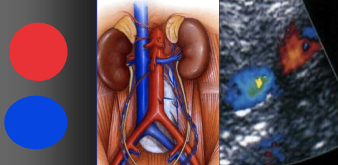

Veine cave Inf

- A faire avec sonde abdominale